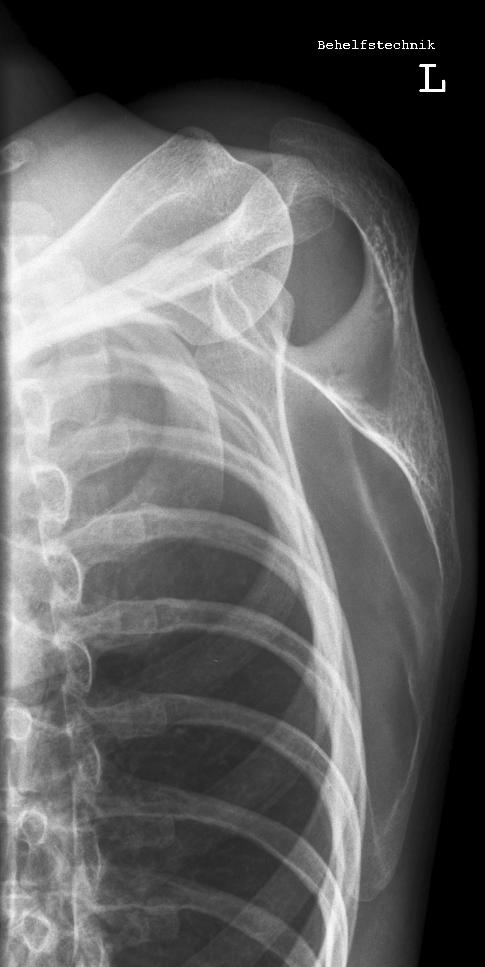

Schulter seitlich

Fehler

Bei dieser Aufnahme wurde der Patient zu weit gedreht, dass somit der Oberarm in den Rippen verschwunden ist. Zudem scheint der Patient einen Buckel gemacht zu haben.

Abhilfe

Abhilfe bringt erstens den Patienten aufrechter hinzusetzen; den Arm richtig lagern, sprich Hand auf dem Bauch und zweitens auf die Drehung von 45° beim Patienten zu achten.